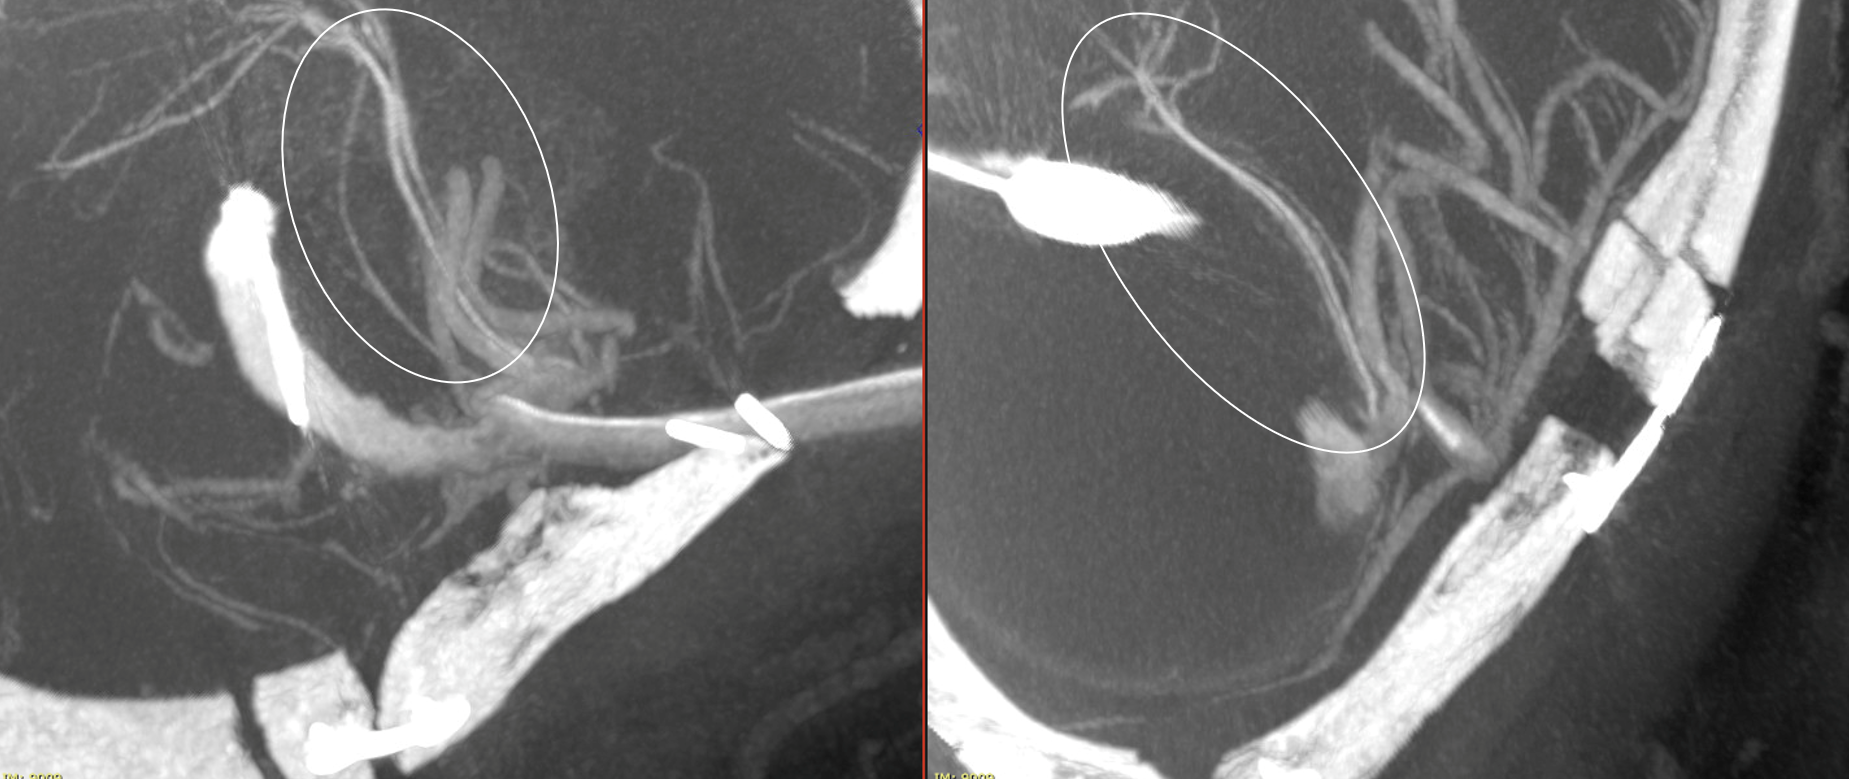

A dual lumen compliant balloon was inflated in the distal segment of the serpentine aneurysm and a Vaso-CT (22 cm FOV, 20 seconds acquisition) was acquired manually injecting pure contrast (300 mg/ml) in the ICA with a 20 ml syringe. It was done to be sure that no perforating arteries originate between the anterior choroidal artery and the bypass. Note the thin metallic filament of the non-radiopaque part of the microguidewire.

Another Vaso-CT was acquired manually injecting pure contrast (300 mg/ml) in the bypass (the injection was visually modulated to avoid reflux in the ICA), maintaining the balloon in place. It clearly shows the M2 perforators originating after the conjunction of the bypass.